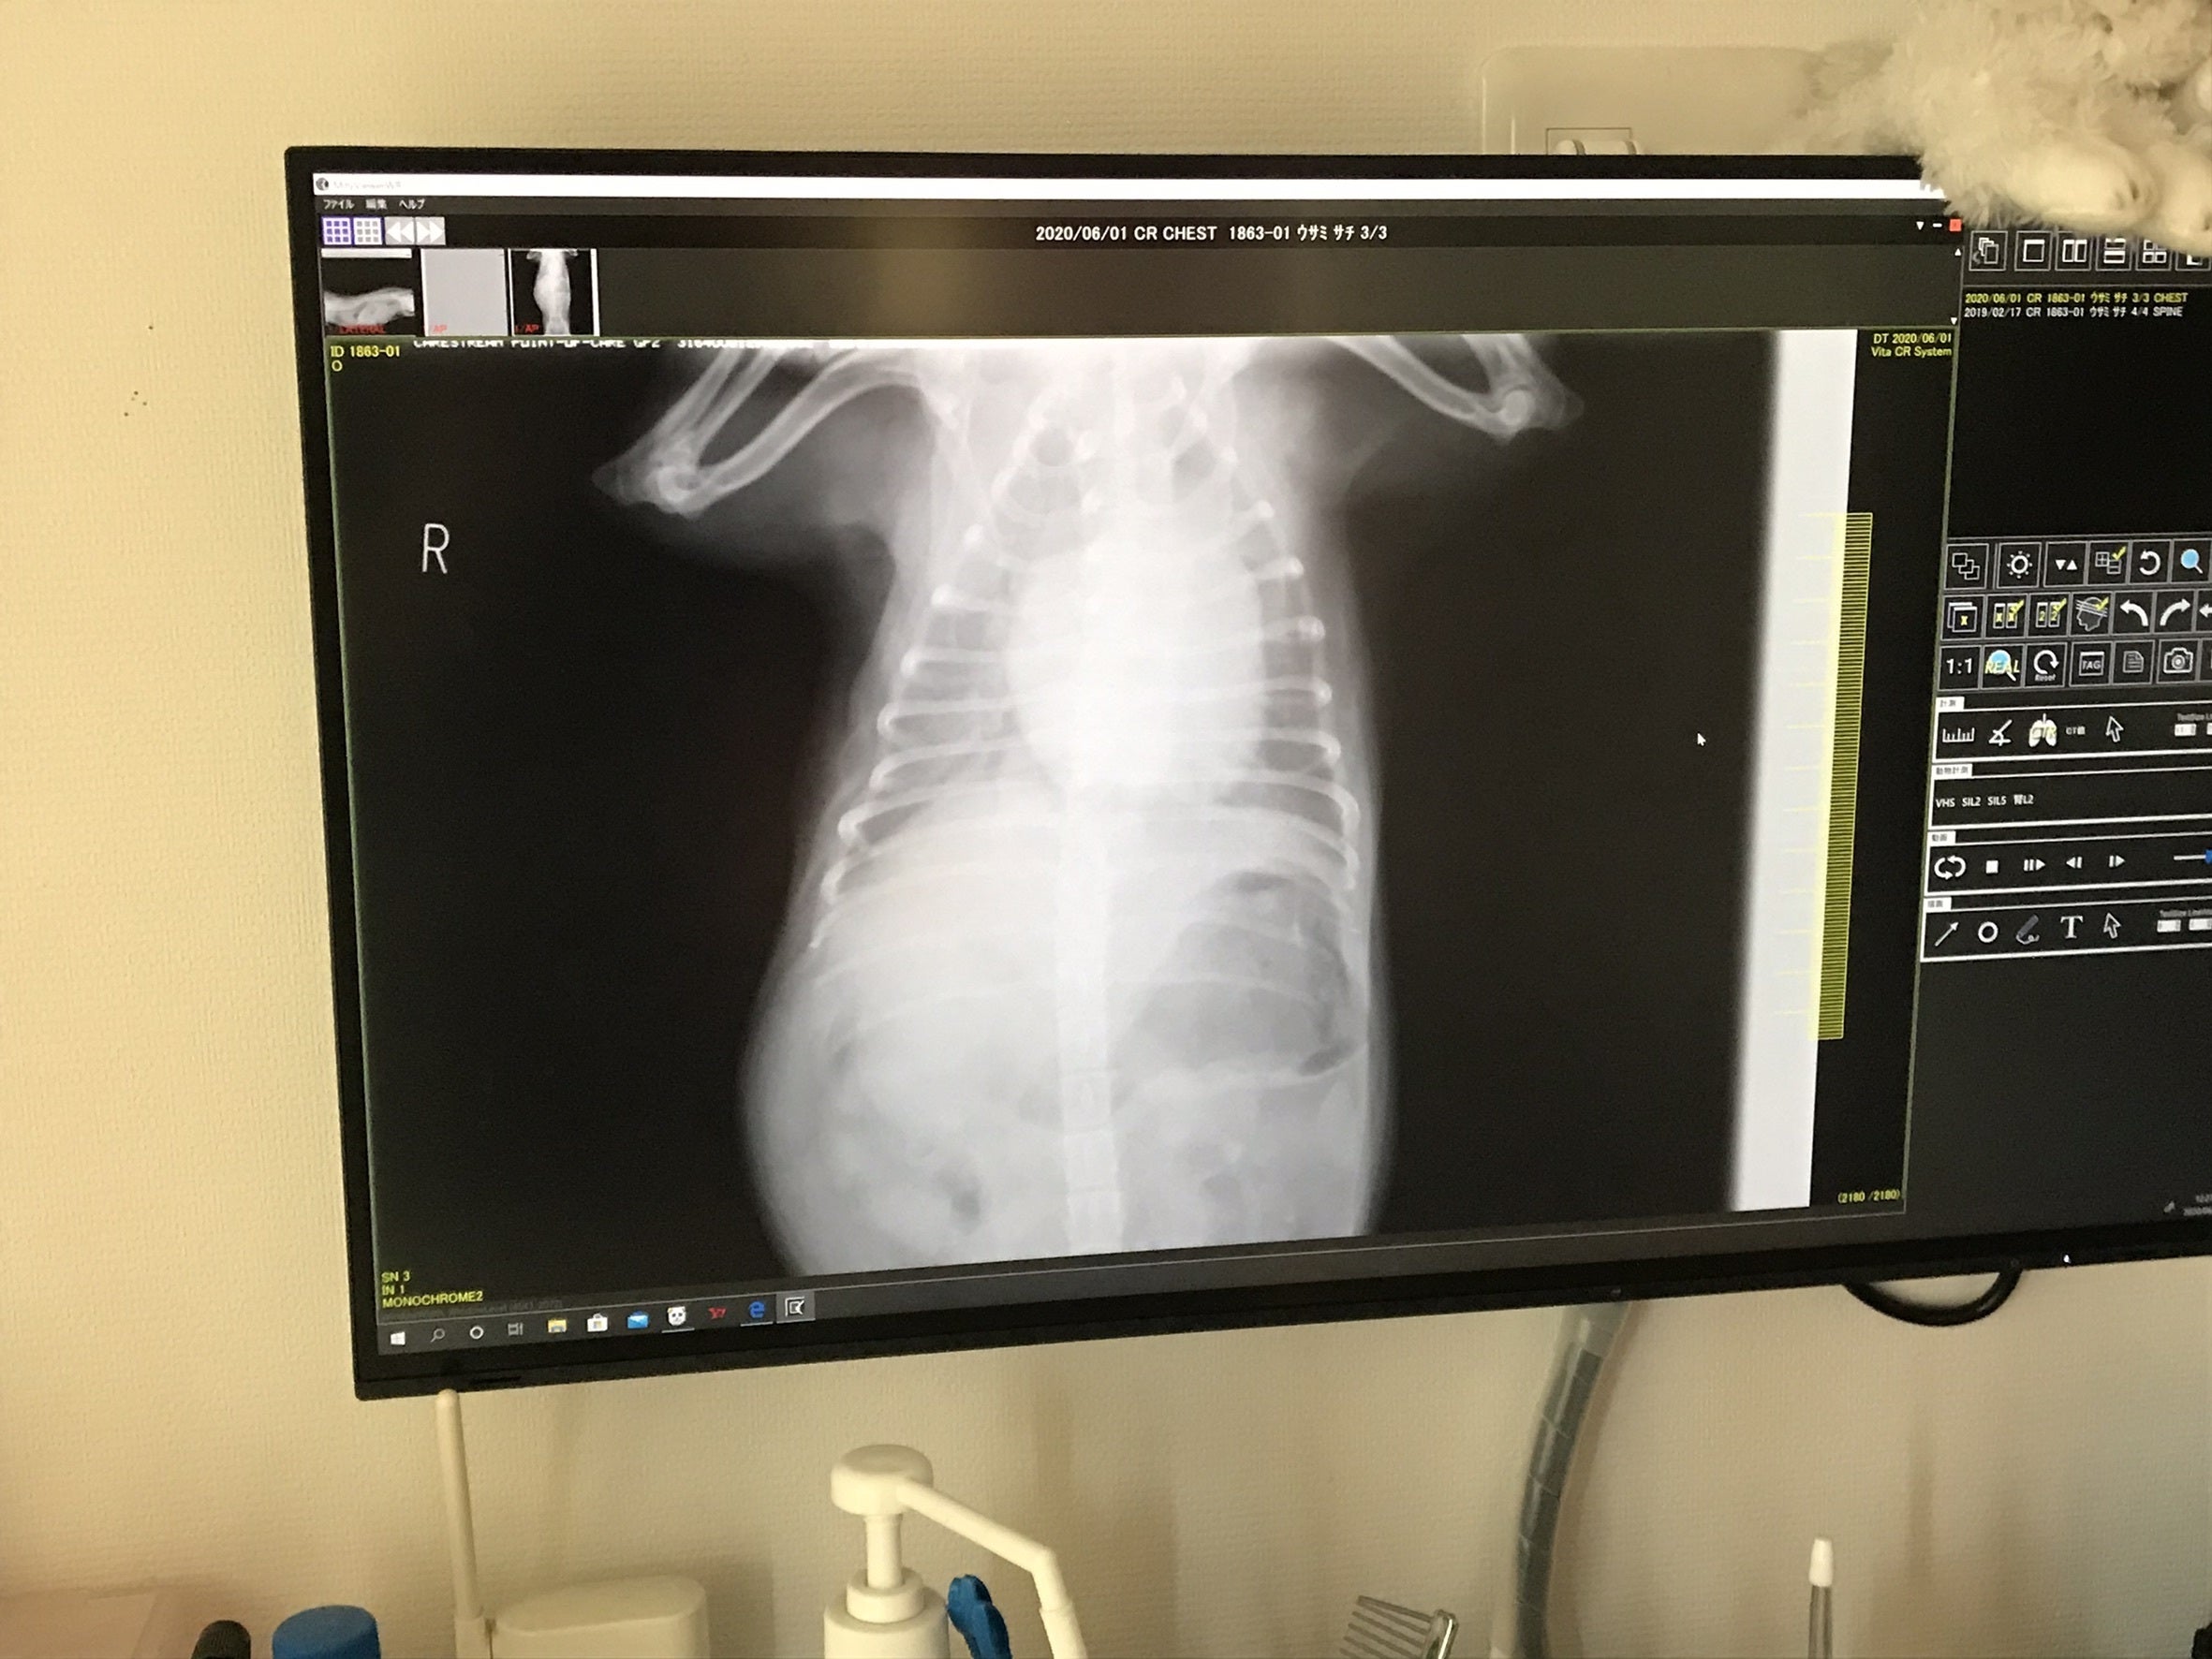

次はレントゲン写真です。心臓が肥大して肺を圧迫しております。血液が逆流するため心臓により大きい負担がかかり、心不全や肺水腫などを引き起こします。この時点で肺水腫を起こし肺に水が溜まっておりました。